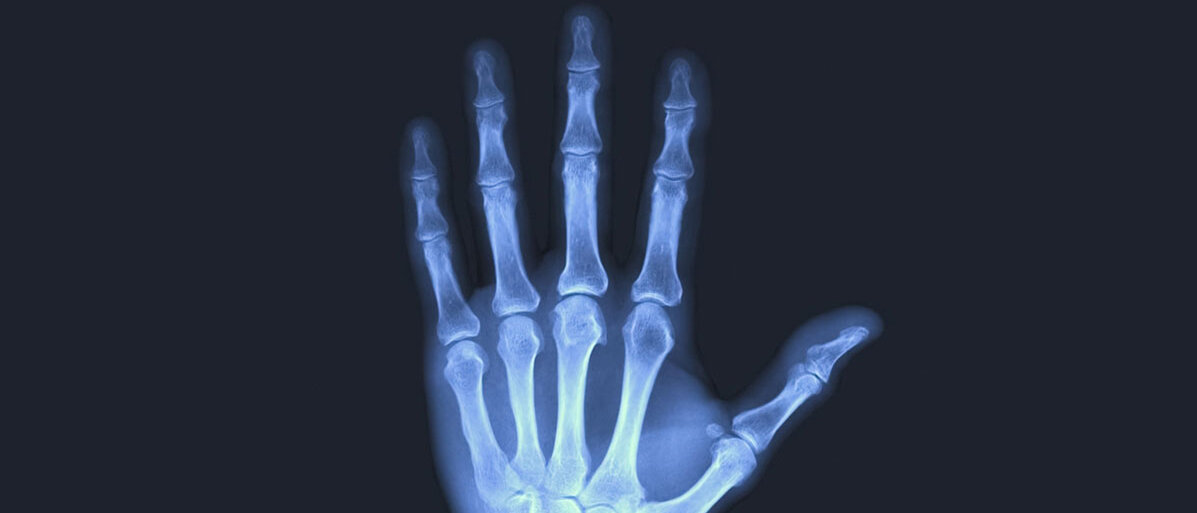

Das Foto von den Handknochen seiner Frau Anna Bertha mitsamt Ring - sichtbar gemacht durch Röntgenstrahlen - ist ein Meilenstein für ganz unterschiedliche Zweige der Wissenschaft. 100 Jahre nach dem Tod von Wilhelm Conrad Röntgen sind die von ihm entdeckten Strahlen, mit denen er die Hand durchleuchtete, unverzichtbar - und längst nicht nur in der Medizin. Forscher rekonstruieren mit ihrer Hilfe jahrhundertalte Morde, mit hochintensiven Röntgenstrahlen lassen sich Viren entschlüsseln, und Röntgenteleskope im Weltraum enthüllen energiereiche, kosmische Prozesse etwa bei Schwarzen Löchern.

Röntgenstrahlen sind extrem kurzwellige, energiereiche elektromagnetische Strahlen, die viele Materialien durchdringen und damit durchleuchten können. Sie sind für das Auge nicht sichtbar. Auf einem Röntgenbild sind Knochen gut zu erkennen, Weichteile dagegen nicht.

Mehr noch: Als er seine Hand irgendwann später - er verbrachte etwa sechs Wochen nahezu Tag und Nacht im Labor - zwischen Röhre und Leuchtschirm hielt, sah Röntgen auf dem Schirm den Schatten seiner Handknochen. So ungefähr soll es sich zugetragen haben an jenem Tag, wie das Röntgen-Kuratorium Würzburg zusammengetragen hat.